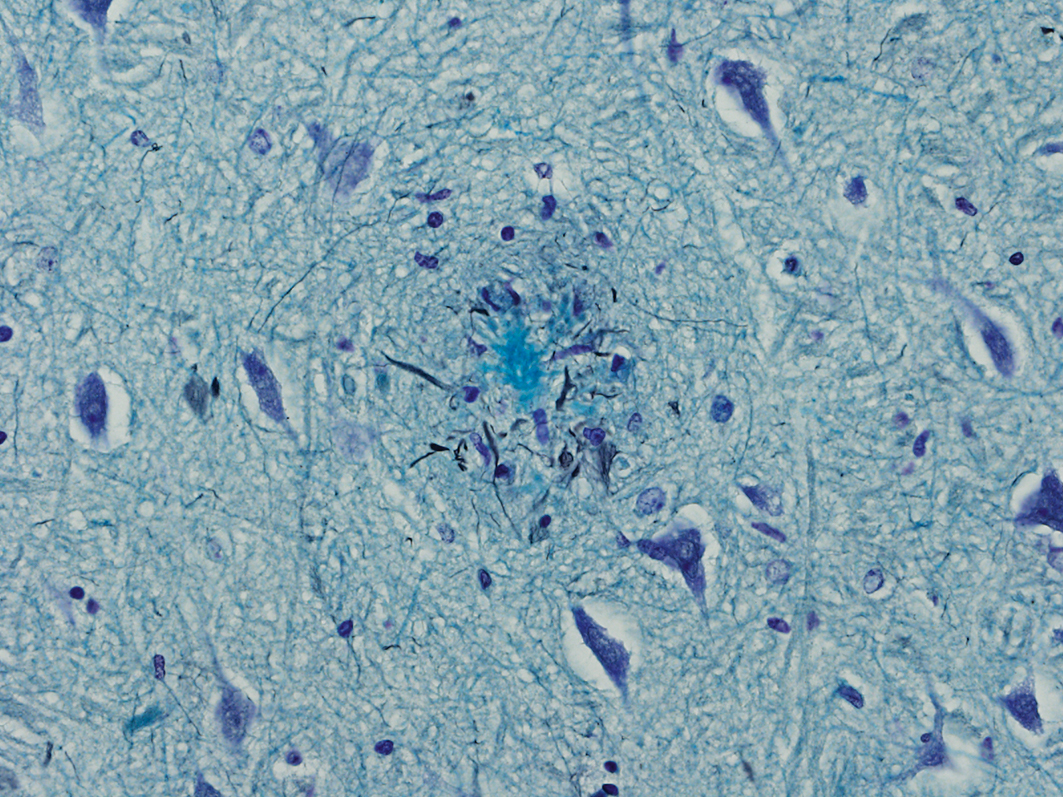

Protein deposits in the brain (so-called plaques) are symptomatic of dementia. The picture illustrates the senile plaques of an Alzheimer’s patient.